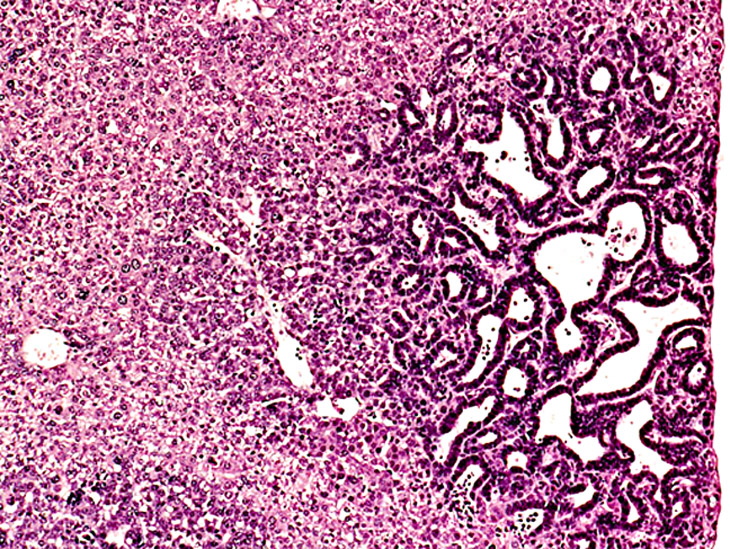

Juxtaposition of a bile duct adenocarcinoma and a hepatocellular adenoma in a 4-week-old transgenic mouse.

Anaplastic cytology is present in this hepatocellular carcinoma in a transgenic mouse.